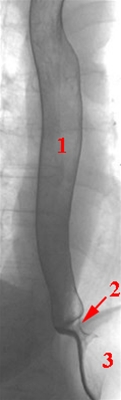

Røngtenbillede af spiserøret (øsofagus) og den nedre ringmuskel (sfinkter) i spiserøret, fremstillet med dobbeltkontrast-teknik

1. Øsofagus (spiserør)

2. Nedre ringmuskel (sfinkter)

3. Mavesæk (ventrikel)